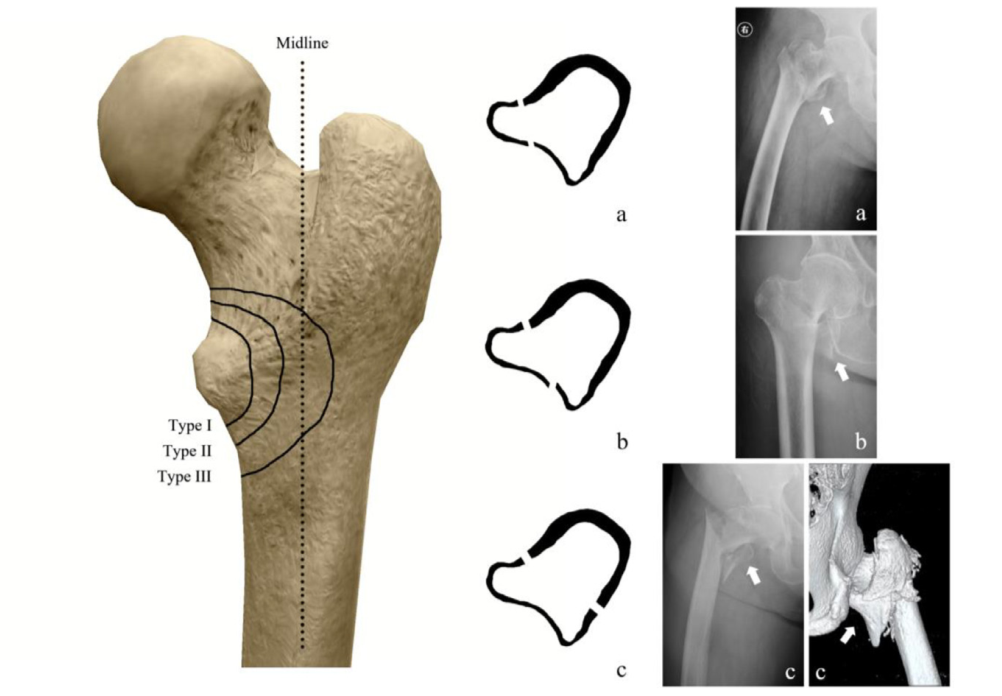

股骨颈骨折内固定治疗的手术技巧,一篇总结到位!